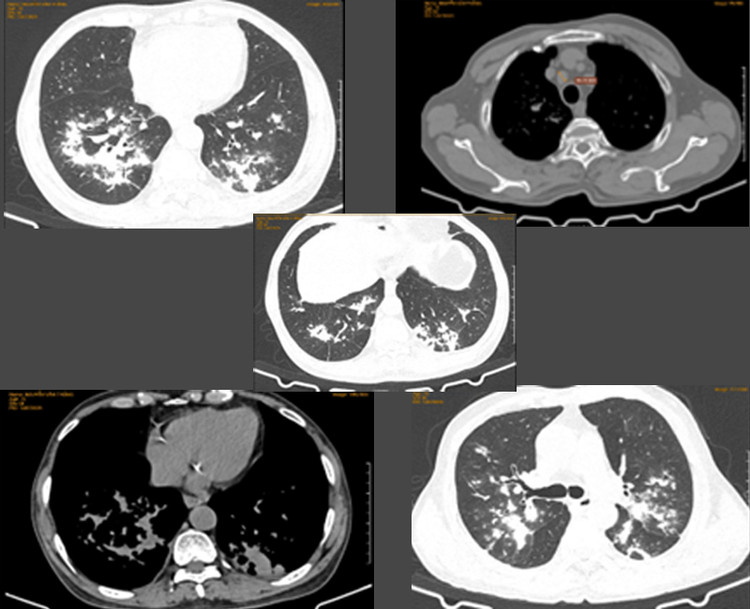

Hình ảnh tổn thương phổi do NTM của các bệnh nhân tại Bệnh viện Đa khoa Hùng Vương (Phú Thọ).Hình ảnh tổn thương phổi do NTM của các bệnh nhân tại Bệnh viện Đa khoa Hùng Vương (Phú Thọ).

Tương tự, thời gian qua, Bệnh viện Đa khoa Hùng Vương (Phú Thọ) tiếp nhận chẩn đoán và điều trị nhiều bệnh nhân có tổn thương phổi. Trong đó, nhiều bệnh nhân ít hoặc không có triệu chứng đã được xác định chẩn đoán viêm phổi do NTM.

Tại Việt Nam, chưa có báo cáo thống kê cụ thể, nhưng ghi nhận bệnh ngày càng được phát hiện nhiều. Tại Mỹ, tỷ lệ nhiễm NTM gia tăng, chiếm 8% (12.000 - 18.000) trong các ca viêm phổi nhiễm mới.